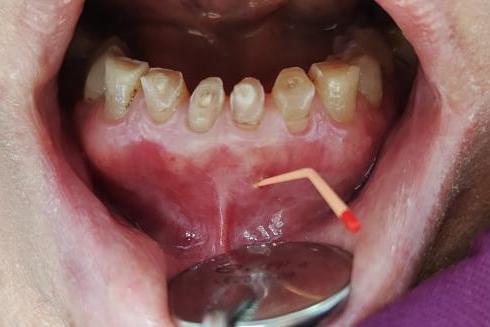

根管治疗术是目前治疗根尖周病的

最有效、最常用的常用的方法。

它采用专用的器械和方法

对根管进行清理、成形,

用有效药物对根管进行消毒灭菌,

最后严密填塞根管,

使得感染得以控制,

促进根尖周病变的愈合。

一般来说成功率为90%左右。

通过完善的根管治疗,

脓包一般都可愈合,

如果失败,也可考虑行根尖手术。